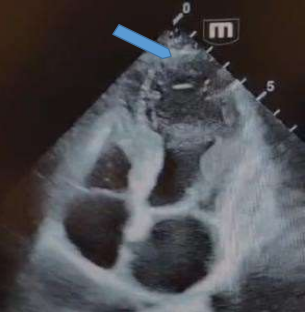

A 39-year-old female with chest pain arrived at the emergency department, H/o no HTN, no DM, not a Smoker, no Family H/o Cardiac disease, Rhinoseptoplasty was performed 3 weeks ago, An electro cardiogram (ECG) was performed Figure 1, which shows ST Segment elevation in pre-cordial leads from V4 to V6 and ST Segment elevation in II, III & aVF. Transthoracic echocardiography (TTE) revealed Global systolic function of the ventricle decreased EF - 40% shows transient wall motion abnormality in apex, septum apical, anterior-lateral, apical segments of the wall Hypo-akinesia Figure 2.

Figure 2 Echocardiography Image Apical Hypokinesis

Transthoracic echocardiography provides a quick method of diagnosing wall motion abnormalities typically seen in apical ballooning syndrome, specifically hypokinesis or akinesis of the midsegment and apical segment of the left ventricle Figure 2.